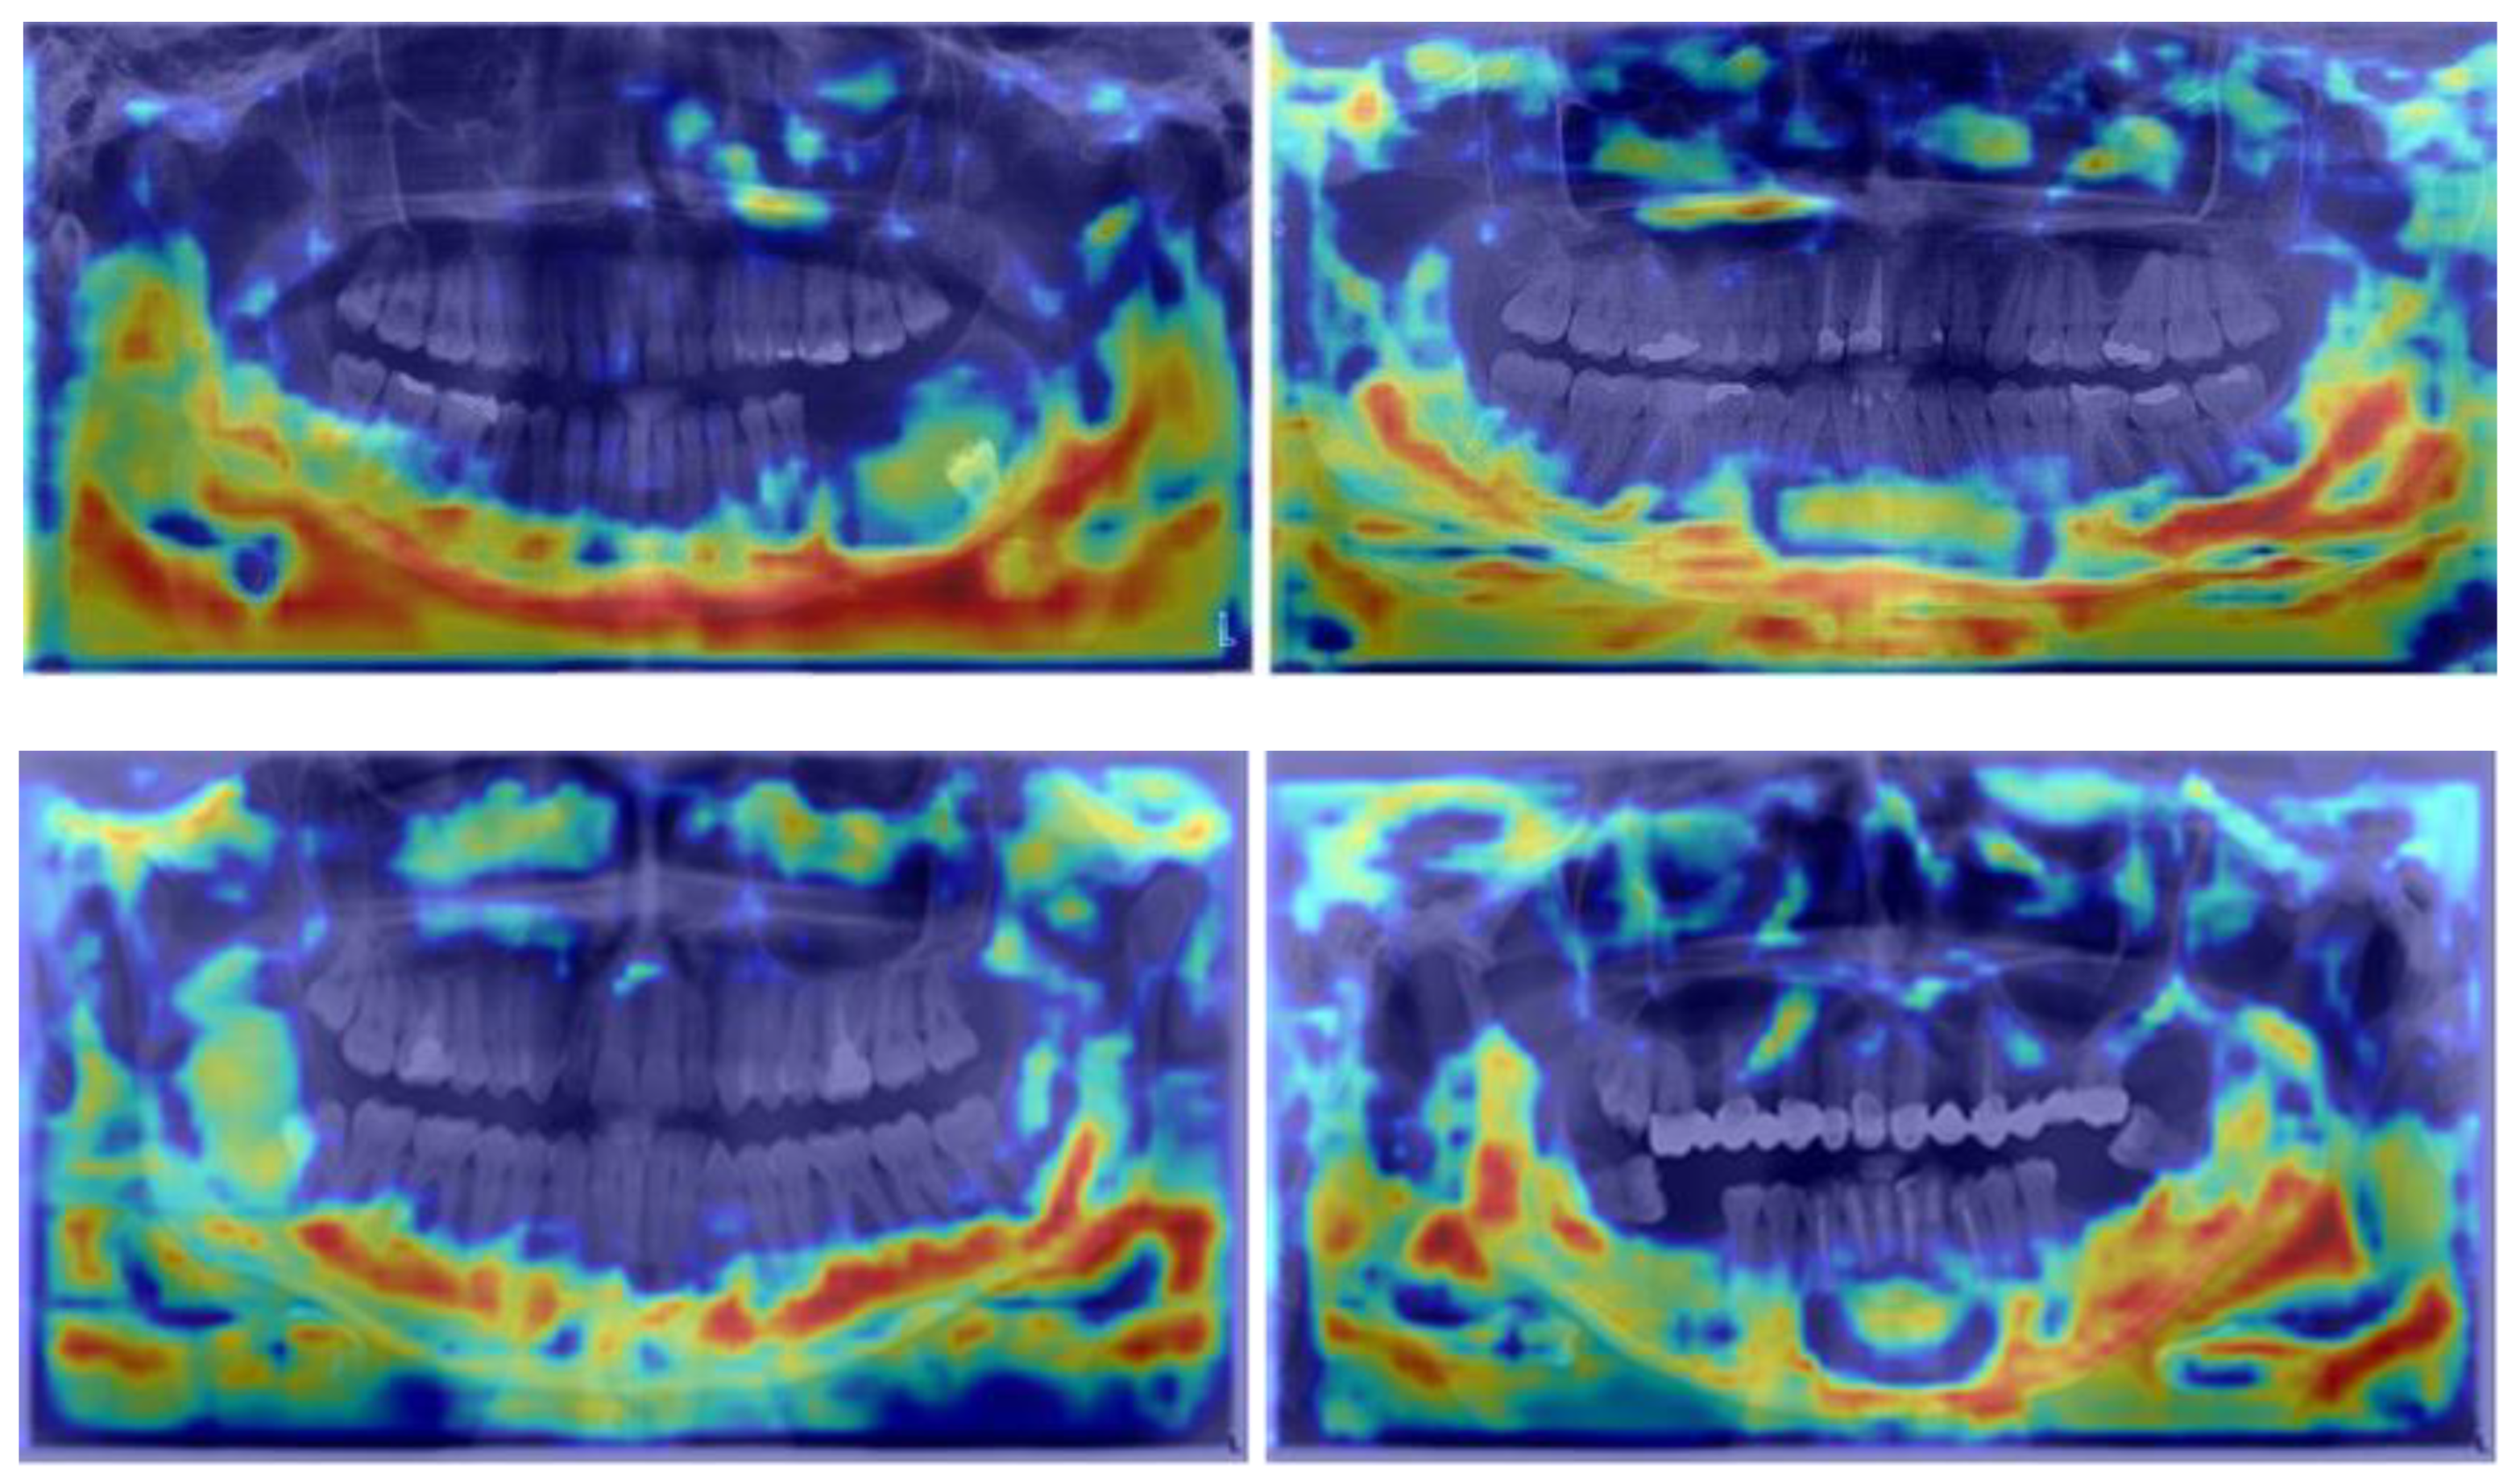

Furthermore, EigenCam was employed to gain deeper insights into the model, as depicted in Figure 6. In thermal imaging, each pixel represents a temperature value. An EigenCAM thermal zone would therefore highlight the areas with temperature variations that are most relevant to the model’s predictions. Additionally, there are some cold zones in the maxillary sinus, indicating that our algorithm faces challenges in distinguishing between the sinus and cysts. The red thermal zone in the lower jaw demonstrates higher accuracy, particularly around the dental roots. The concentration of intensity on the thermal map around the area of the lower jaw confirms the previous assertion and highlights the model’s capability to discern features pertinent to detecting mandibular cysts.

Innovative visualization techniques, such as EigenCAM, further enrich our understanding of how models make predictions. EigenCAM generates heat maps that visually represent regions the model deems crucial for its predictions. These maps offer a clear visual insight into parts of the image critical for recognizing pathological conditions, often highlighting specific regions, such as the lower jaw, with heightened intensity, emphasizing potential locations of radiolucent lesions (Figure 6).

Figure 6. An intensified thermal zone is visible in the lower jaw area.